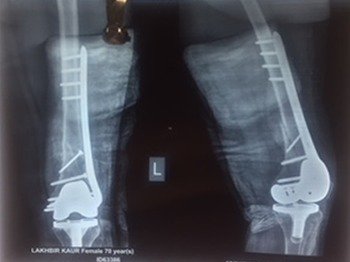

Fracture of soft bones in children needs to be delicately treated with plasters or minimally invasive and least traumatic surgeries. In addition, he specializes in the correction of limb deformities in children with polio, cerebral palsy etc.

Osteoporotic bones with newer techniques to make patient ambulatory as early as possible.